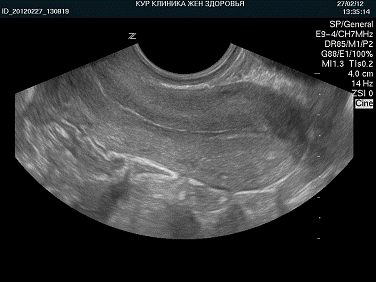

Диагностические возможности УЗД хорошо

реализуются в диагностике первичных и вторичных опухолей и сопутствующей

патологии печени, поджелудочной железы, селезенки, почек, простаты, матки,

внеорганных и брыжеечных новообразований брюшной полости, забрюшинного

пространства и малого таза. УЗД при опухолях желчного пузыря, яичников и

надпочечников имеет высокую чувствительность при малой специфичности (выявляет

соответствующие изменения, но не позволяет уверенно провести дифференциальную

диагностику). Основное предназначение УЗД - получение прямого непосредственного

изображения опухоли (гиперэхогенные и гипоэхогенные образования) и

сопутствующих изменений.

УЗИ печени УЗИ почек

УЗИ пожделудочной железы

УЗИ матки

УЗИ мочевого пузыря УЗИ желчного пузыря